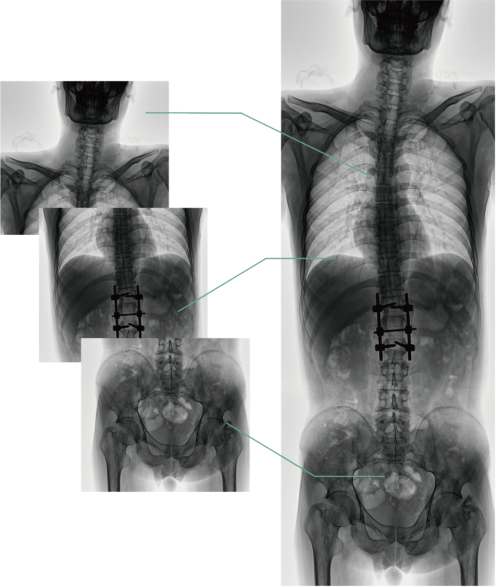

四、圖像自動拼接

圖像自動拼接功能實現(xiàn)全脊柱、全下肢全景攝影,解決在觀察頸椎至尾椎的脊柱側(cè)彎或其他病變時不能一次成像的問題,能夠直觀的顯示脊柱和下肢的整體解剖形態(tài)及側(cè)凸部位。